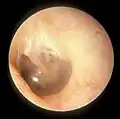

The oval perforation in this left tympanic membrane was the result of a slap on the ear

A subtotal perforation of the right tympanic membrane resulting from a previous severe otitis media